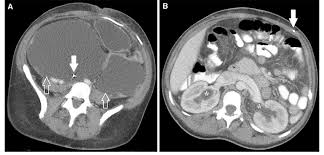

Axial Ct Images Through The Abdomen And Pelvis Of A Patient With Vp Download Scientific Diagram